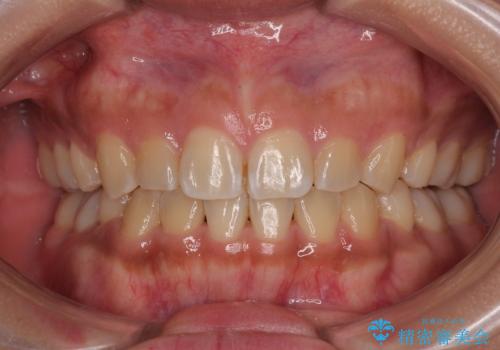

受け口と八重歯を改善 インビザライン矯正治療